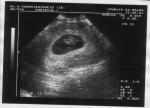

Album: Wat voorafging

Enkele foto's van de 9 maanden vooraf